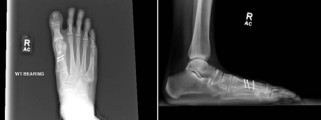

A twenty-five year old female runner and career model presented with chronic right forefoot pain along the first ray as well as the lateral aspect of the fifth ray. She reported a history of previous surgery, at the age of eleven, for hallux valgus deformity, which included pinning across the first MTP joint. After her initial surgery, she experienced worsening pain, increased stiffness, and recurrence of the hallux valgus deformity. Upon physical examination of her forefoot, a prominent hallux valgus deformity was noted with painful bossing at the dorsal aspect of the first MTP joint. Palpation revealed tenderness at the first MTP joint at the medial eminence as well as dorsally at the first metatarsal head. Range of motion was limited to less than 20 degrees of dorsiflexion from the floor. Radiographic assessment revealed degenerative changes at the first MTP joint with subchondral sclerosis, subchondral cyst formation, and mild joint space narrowing. The preoperative hallux valgus angle was 25 degrees and the inter-metatarsal angle was 8 degrees. The fifth ray exhibited a prominent bunionette deformity with curvilinear lateral deviation of the 5th metatarsal shaft (Figure 1).

Figure 1: Pre-op Imaging.